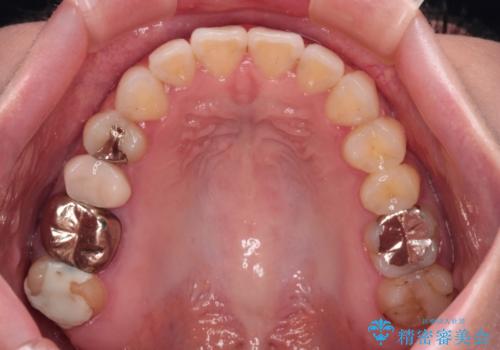

前歯のデコボコをすっきりと インビザライン矯正

- 前歯のデコボコを治したいとのことで来院された患者様です。

下顎が前方位にある方であったため、下顎の歯列全体の後方移動とIPR(歯と歯の間を削る)によってデコボコが解消するように設計し、インビザラインにより治療を行うこととしました。

装着時間が守れず、当初の予定よりも長期間必要となりました。